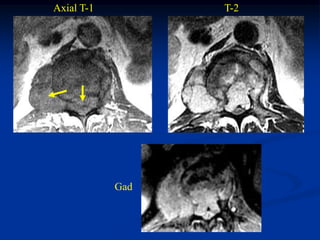

Case #1101

Axial T-1 MRI

60 year female with chordoma sacrum

Axial T-2 MRI

Sagittal T-2 MRI